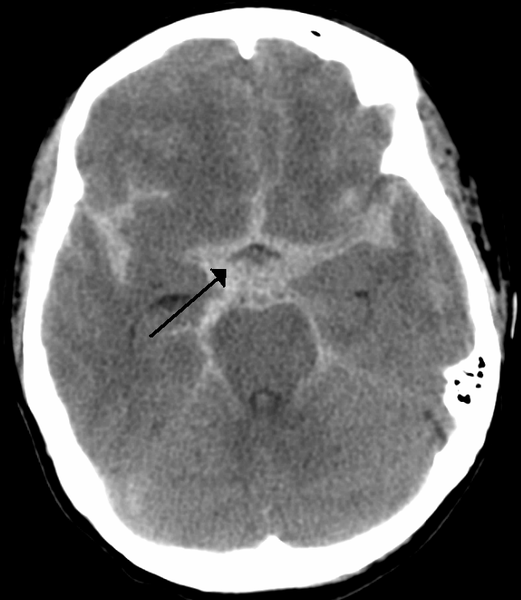

- Subarachnoid Hematomas: Occur when there is bleeding into the space between the arachnoid membrane and the pia mater that surrounds the brain.

Figure: Subarachnoid Hemorrhage. Image courtesy of Dr. James Heilman. Image used under the Creative Commons Attribution-Share Alike 3.0 Unported license.